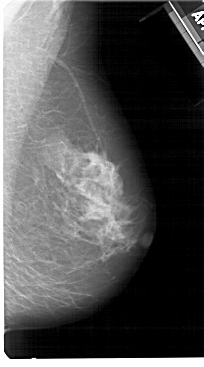

A_1512_1.RIGHT_CC

RIGHT_CC LINES 5371 PIXELS_PER_LINE 2701 BITS_PER_PIXEL 12 RESOLUTION 43.5 NON_OVERLAY